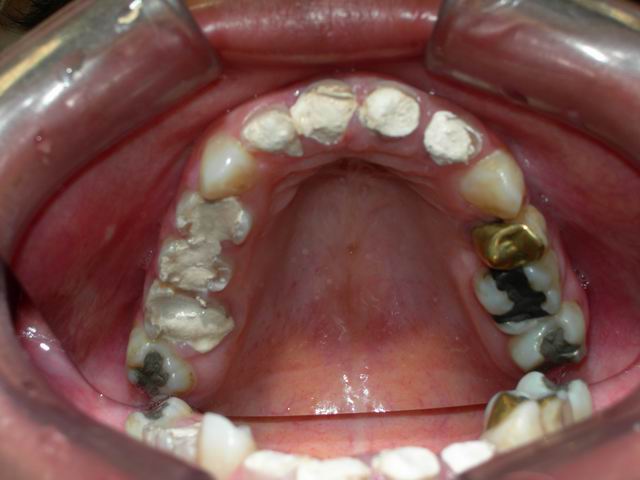

Imagem especular da maxila em fase prévia aos desgastes de preparação protética